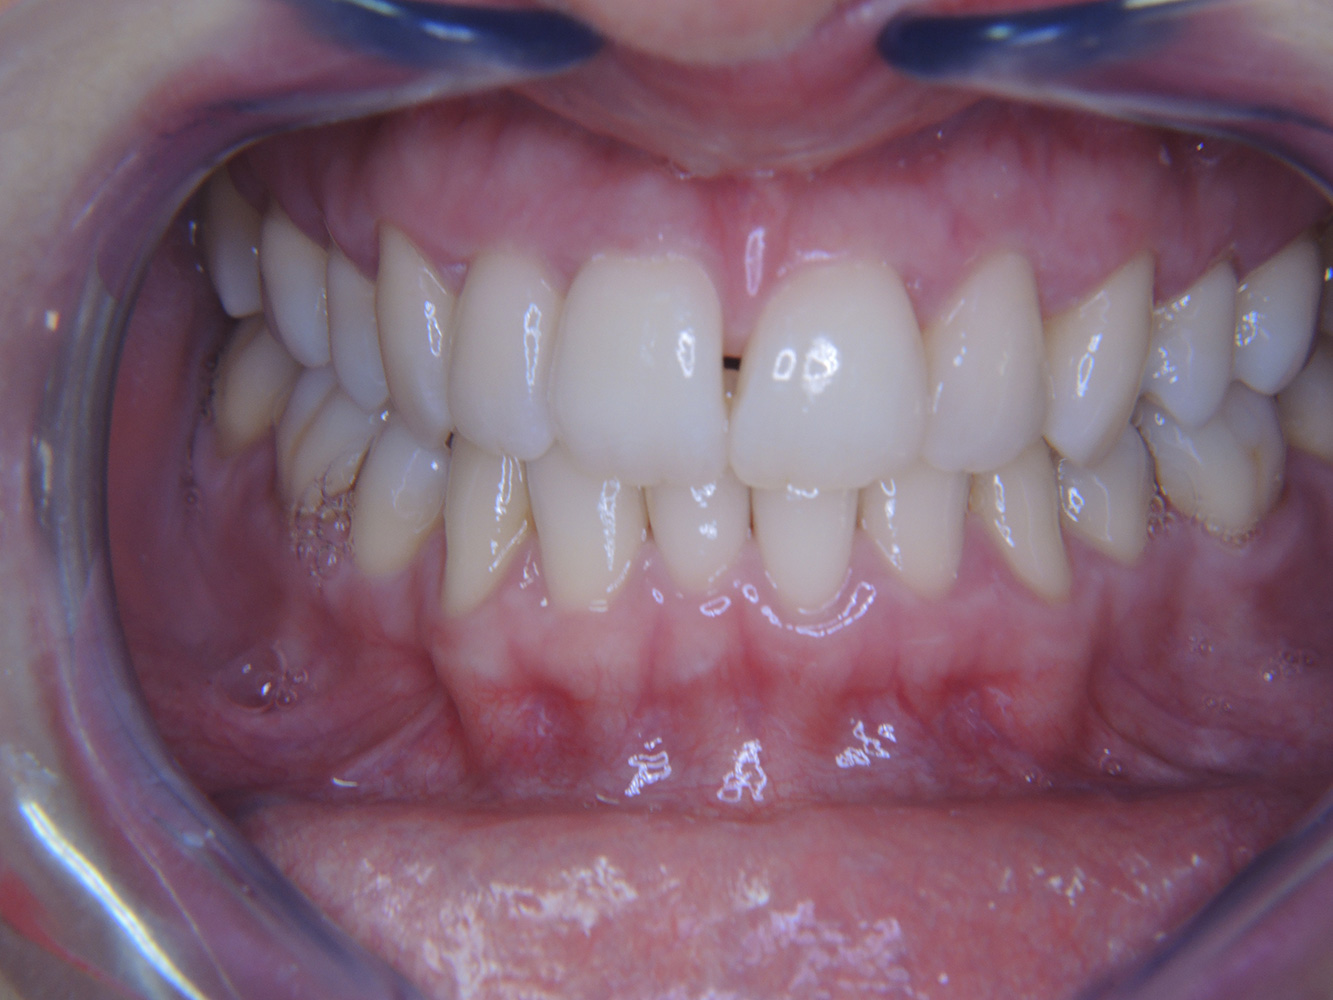

Der gesunde Patient mit parodontaler Vorerkrankung & Periimplantitis